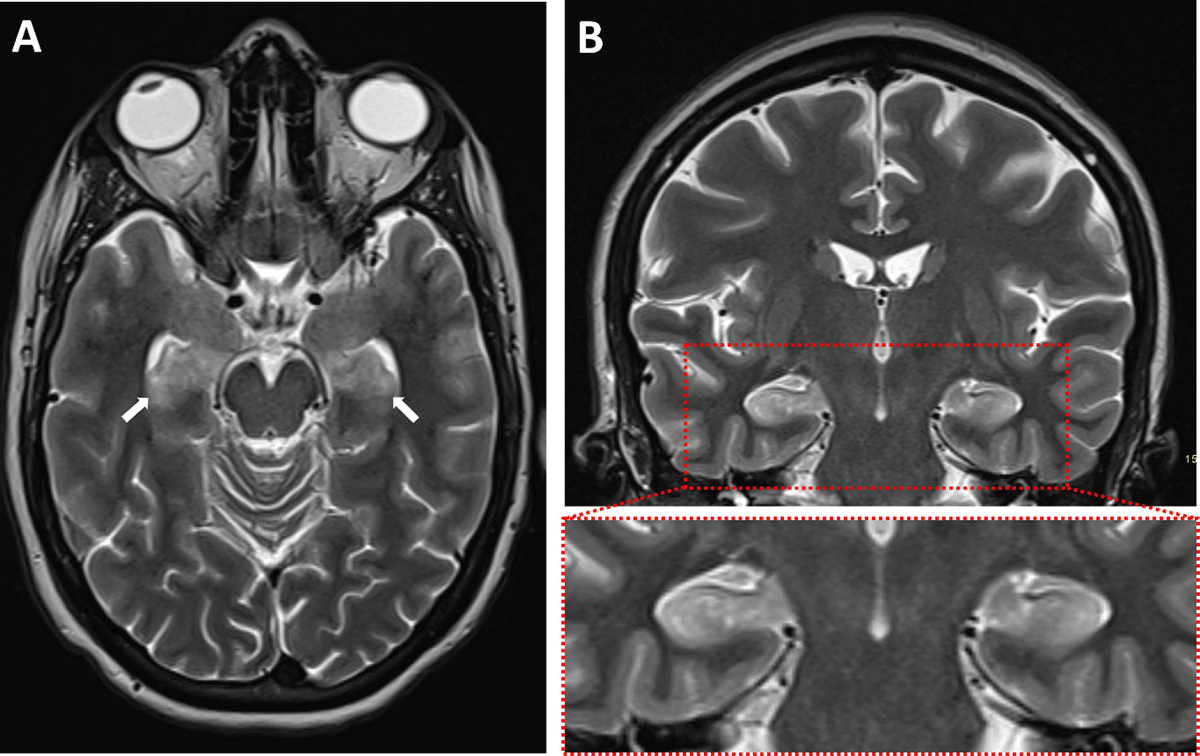

A 39-year-old woman who recently suffered an influenza-infection presented at the ER because of confusion, hallucinations, and progressive neurological decline. During her hospitalisation, she developed focal myoclonic epilepsy which transformed into status epilepticus. Magnetic resonance imaging (MRI) of the brain showed bilateral T2-hyperintense changes in the mesiotemporal structures on axial FLAIR-weighted images (Figure 1, arrows) and on axial and coronal T2-weighted images (Figure 2A–B respectively, arrows). Additionally, a bilateral T2-hyperintense claustrum was seen on axial T2 and axial and coronal FLAIR-weighted images (Figure 3A–C respectively, arrows). Lumbar puncture showed mild pleiocytosis and mildly elevated protein levels. Viral serological and PCR tests were negative. Clinical findings without detection of an acute seizure cause are compatible with febrile infection-related epilepsy syndrome.

Figure 2

The role of imaging is mainly to rule out encephalitis or another structural seizure cause. The majority of (initial) imaging studies in FIRES are normal. When abnormalities are present, these often consist of T2-hyperintense changes in the mesiotemporal regions, with or without signal changes in the basal ganglia or peri-insular region [1]. Evolution to hippocampal sclerosis in the chronic phase is possible.